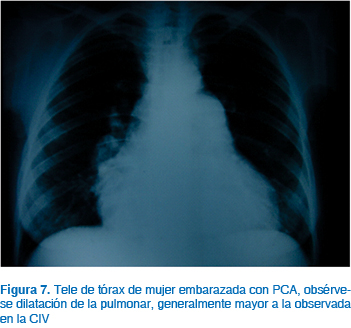

No obstante, en pacientes con cortocircuito de izquierda a derecha con hipertensión pulmonar de leve a moderada, el embarazo y el parto son bien tolerados; sin embargo, las pacientes con insuficiencia cardiaca con frecuencia requieren vasodilatadores, diuréticos y digoxina. La hipovolemia, el uso de vasodilatadores y las condiciones que generan disminución de las resistencias vasculares sistémicas pueden generar la inversión del cortocircuito, es decir, de ser de izquierda a derecha cambia a ser de derecha a izquierda apareciendo cianosis y síndrome de Eisenmenger. Por esta razón, las pacientes con hipotensión en el parto o postparto pueden recibir vasopresores. La anestesia regional es la más indicada, y para la resolución del embarazo, la vía vaginal; al igual que en otras lesiones, se reserva la vía abdominal para las indicaciones obstétricas convencionales (Figuras 7 y 8).